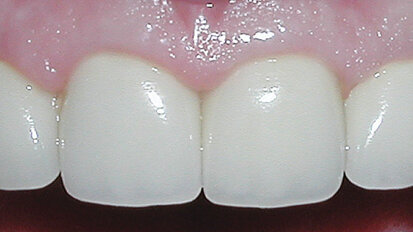

Our 58-year -old patient had a lifetime of periodontal disease and rampant decay. As a young woman, Donna’s dental disease was diagnosed and treatment...

save